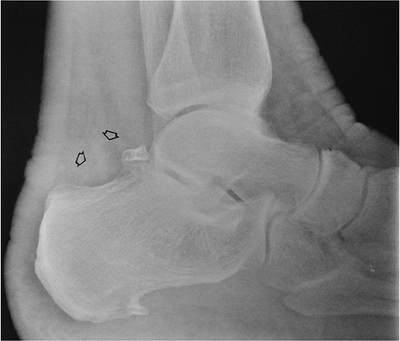

FIGURE 6-58 Computed radiography lateral view of the ankle showing an os trigonum with edema in the pre-Achilles fat (open arrow) caused by os trigonum syndrome.

FIGURE 6-59 MRI of os trigonum syndrome. Sagittal (A) and axial (B) T2-weighted images showing fluid in the region of the os trigonum (arrowheads in A) and edema (open arrow) and tendon sheath fluid (arrowhead) around the flexor hallucis longus tendon because of associated tendinitis.